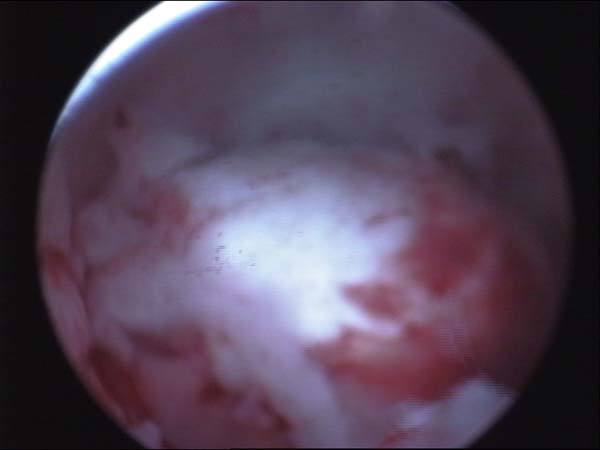

- Hysteroscopy Video clips

- Hysteroscopy Photos

Hysteroscopy Pictures | Dr N Layyous